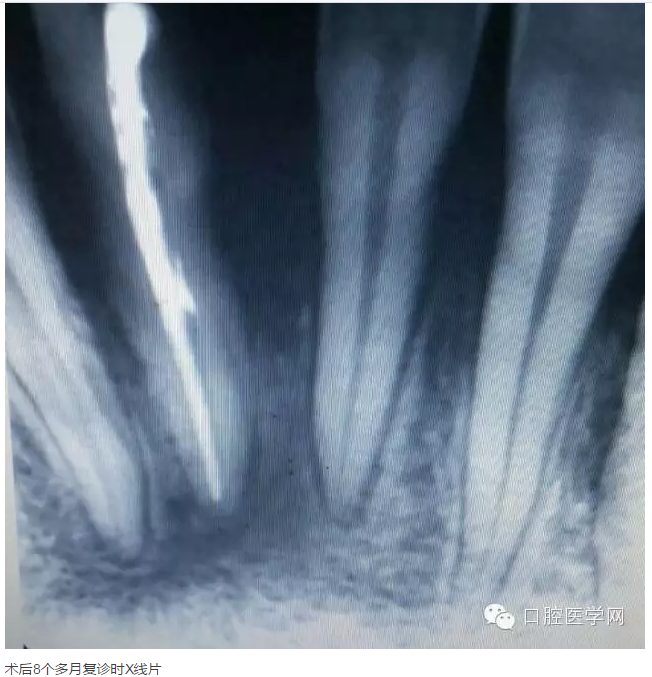

下面是一例 今年年初治療的下前牙根尖囊腫病例,患者因故未能按時(shí)復(fù)診,最近才來(lái)。